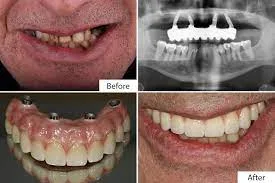

Digital Dental Implants Before and After (Photo Results)

Digital dental implant treatment often produces highly predictable and aesthetically pleasing results. Before-and-after images typically show:– Replacement of missing teeth with natural-looking restorations – Improved smile line, tooth shape, and alignment – Restoration of facial support in areas of bone lossYour dentist can show you actual case photos that match your situation to help you understand the expected outcome.